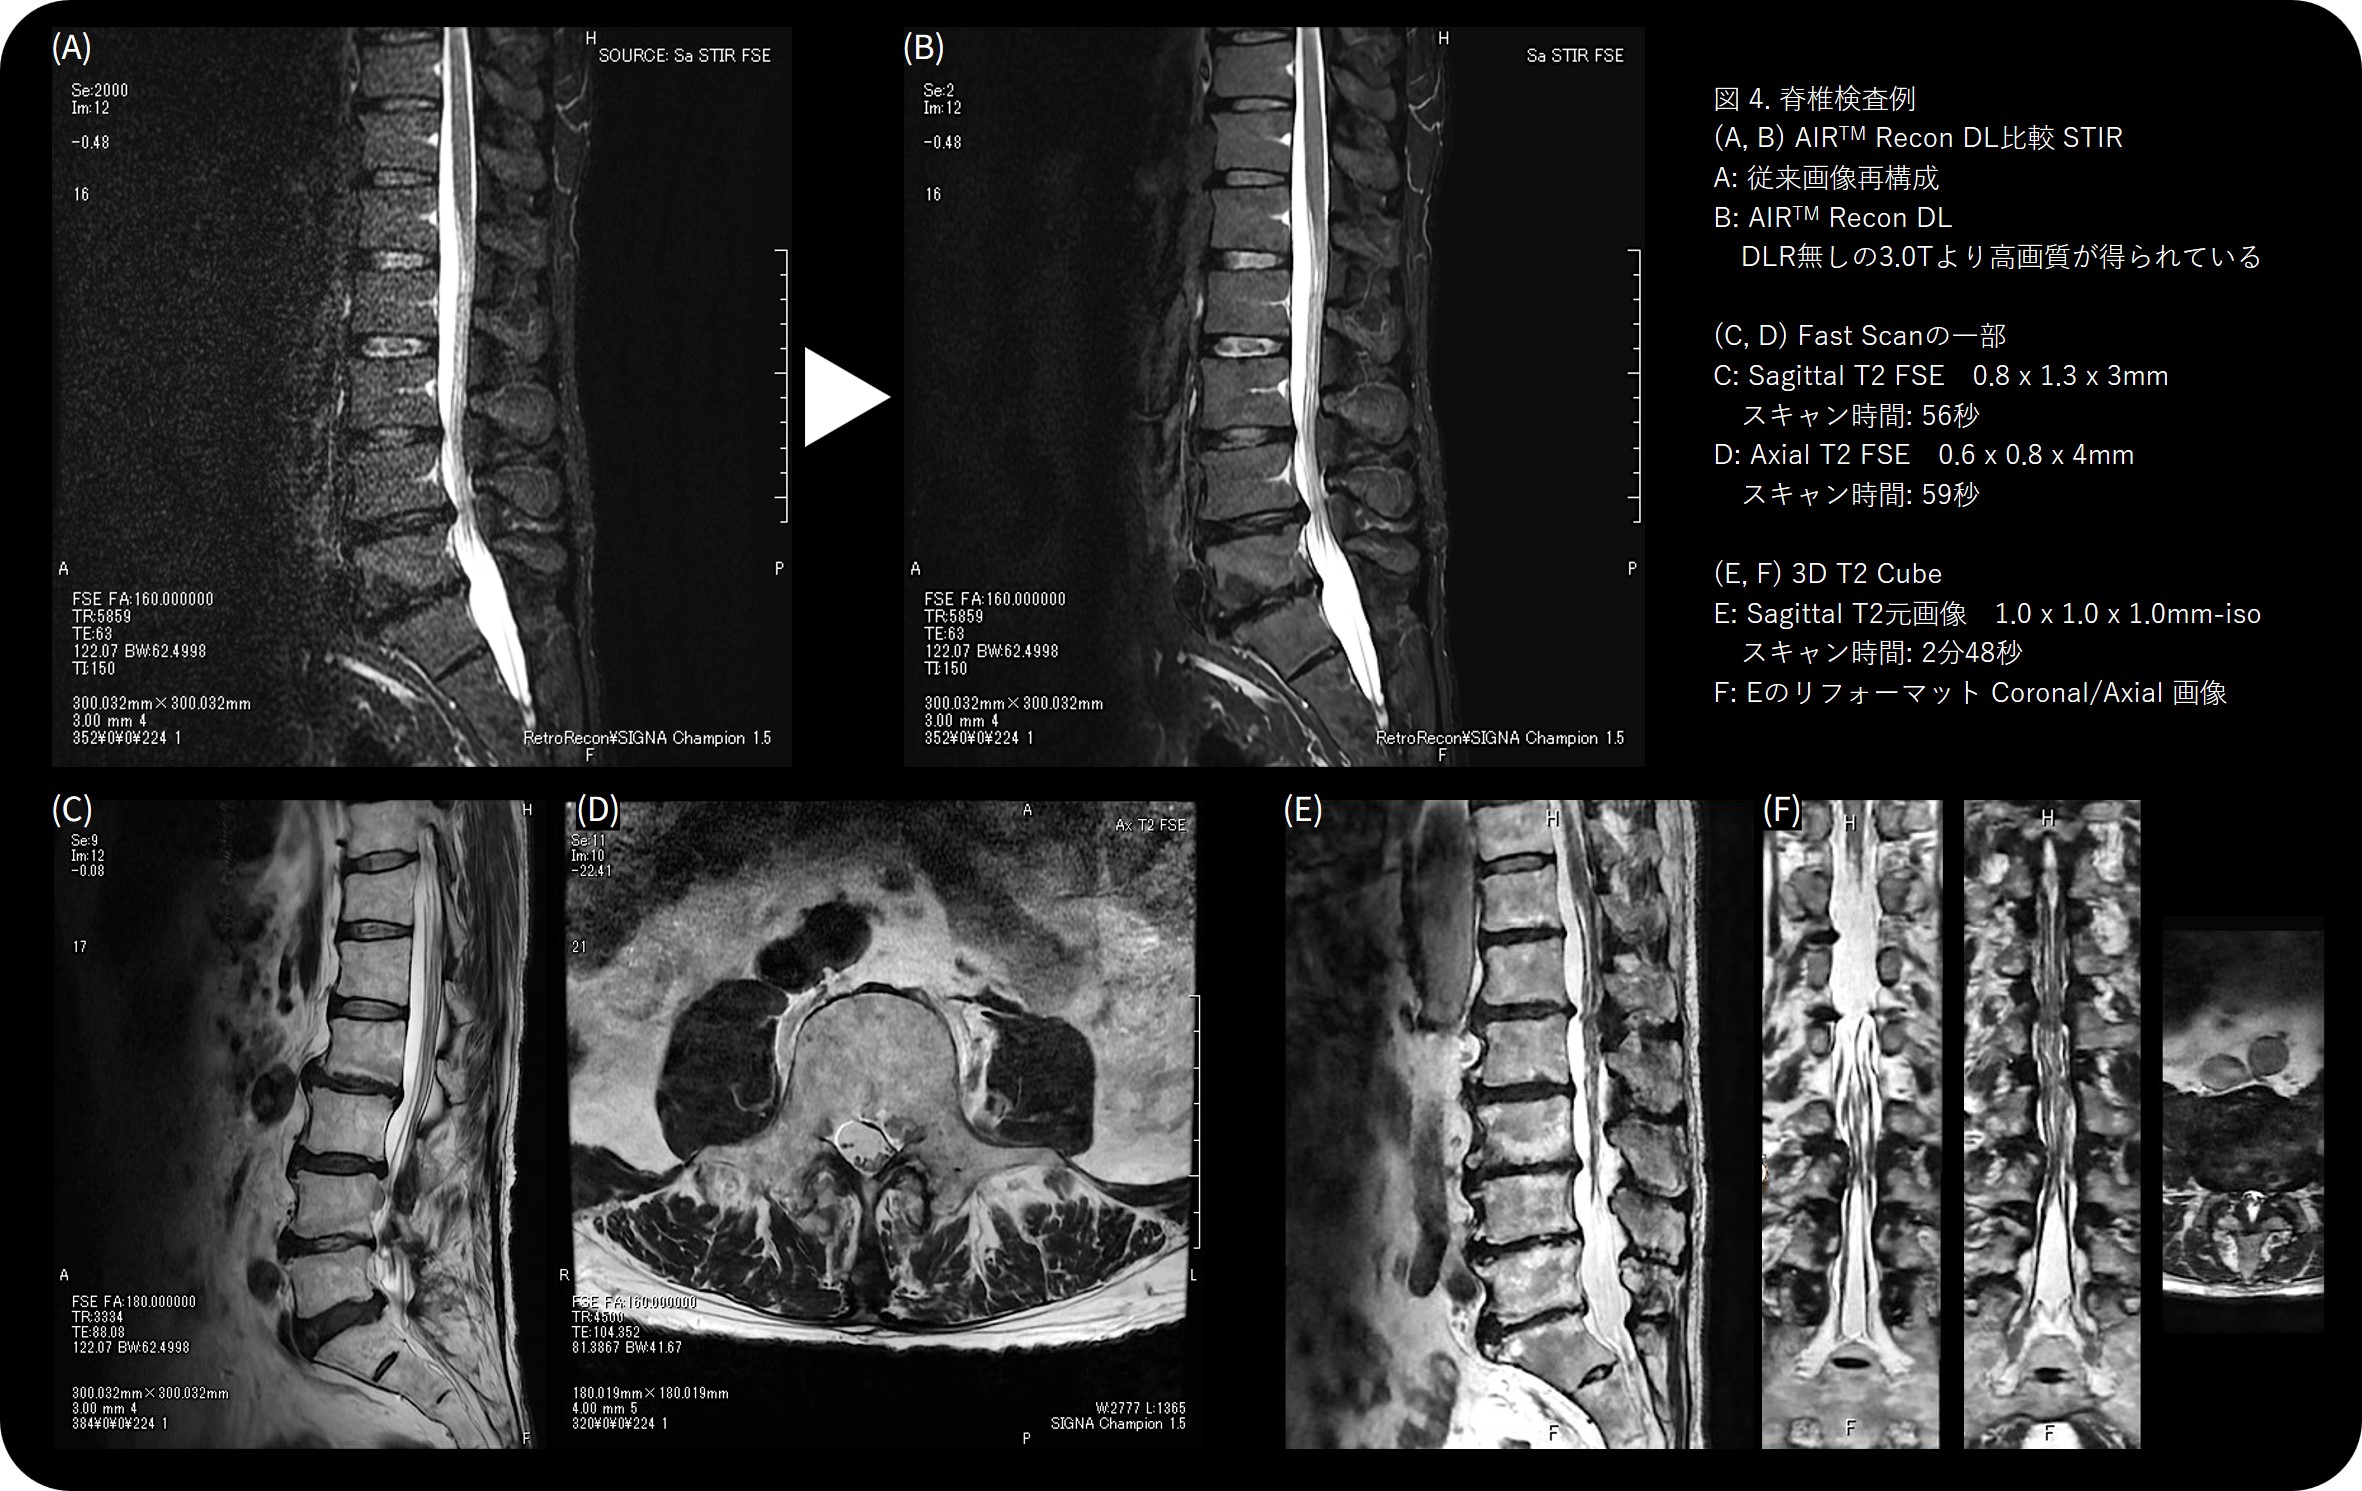

導入後、最も印象的だったのは、短時間でも高画質が維持される点です。 (図5-7)

34秒のSagittal T2w撮像では、従来法に比べ動きに強く、ルーチン撮像を置き換えることができました。この画像を見て「ルーチンを変えよう!」と即決しました。現在ではFast scanを34秒、通常スキャンも50秒台に変更しています。

従来20年間使い続けてきたgapless DWIのルーチンが(前装置ではSNR等の観点から諦めていましたが) 最新技術によって再評価され、新たな形で “復活” もしました。さらに厚みの設定によるSNR変化への理解も深まりました。3.0mmでは明瞭に見える信号が、5.0mmにするとボケてしまうケースもあり、厚みを細かく調整することで診断能を最大化できることを実感しています。 AIR™ Recon DLでは、高SNRと高分解能を両立できるため、1分半の短時間撮像でも高画質が維持される点が特に印象的です。